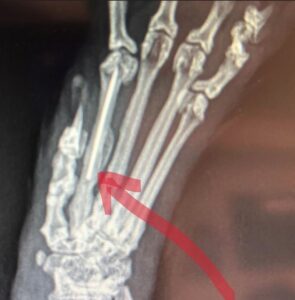

Our vet staff soon discovered a fracture in Ryder’s paw after collecting radiographs (x-rays) and performing an exam in which Ryder was temporarily sedated, called an anesthetized exam. When medically evaluating wild animals like Ryder, we always take the necessary precautions to keep ourselves and the animals safe—he’s not your average house cat, despite his looks!

Ryder’s foot was initially splinted following his exams, but after consulting Board-certified Veterinary Surgeon Dr. Sylvia Lee at MedVet, an innovative approach to repairing a small foot fracture was performed. The repair was successful thanks to the partnership between Hogle Zoo and MedVet and their dedication to care.